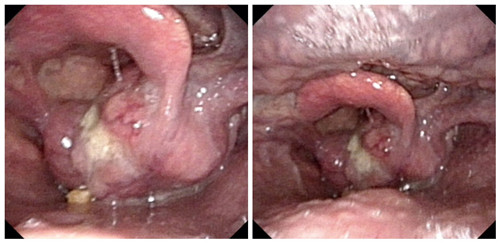

术前喉镜

患者54岁,男性,因声音嘶哑、气短2月、呼吸困难2天就诊,以“喉肿物、呼吸困难”急诊入院。入院后,段世宏主任团队结合患者病史及临床表现,完善相关检查后确诊为下咽癌侵犯喉和右侧甲状腺及颈内静脉,伴右颈部淋巴结转移。经过充分讨论及精心准备,5月7日,联合口腔科孙健主任共同为患者实施了全喉及全下咽切除+右侧根治性颈淋巴结清扫+右侧甲状腺叶及峡部切除+胸大肌皮瓣修复手术,手术全程用时12小时,术后患者恢复良好,已康复出院。